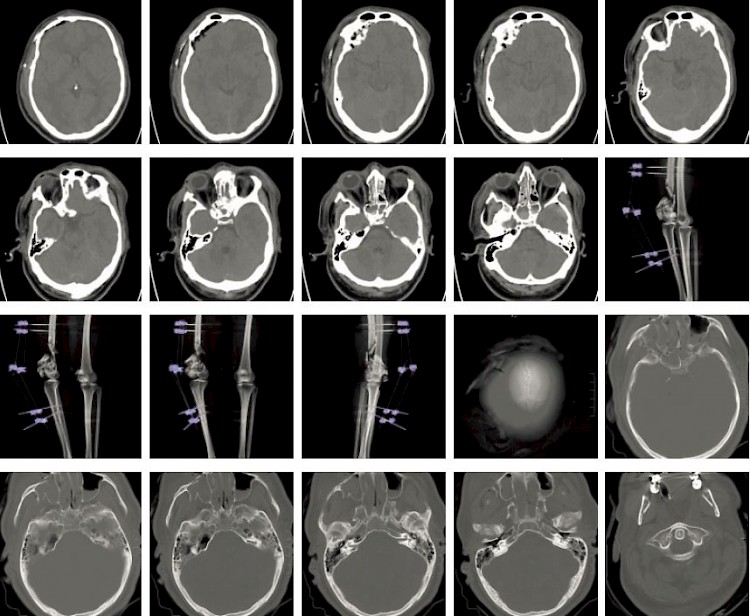

Fallbeispiel

Schädel-Hirn-Trauma nach Verkehrsunfall

Ein Autofahrer war auf der BAB unterwegs, bis er von der Fahrbahn abkam. Er wurde mit dem RTW in das nächste Krankenhaus gebracht, wo er dann als Polytrauma-Patient im Schockraum behandelt wurde.

Primär wurde eine Beckenübersichtsaufnahme und ein Rö-Thorax angefertigt. Nach der Erstversorgung wurde der Mann ins CT gebracht, wo dann das Traumascan gefahren wurde

Nachstehend einige Bilder des Traumascans.

Befund:

- Schmales subdurales Hämatom Li temporal und re frontal.

- Deutliche Hirnschwellung.

- Ausgedhnte Gesichtsverletzung mit Beteilung der Frontobasis und der Schädelkalotte re frontal.

- Fraktur der mitteleren Schädelbasis und des Felsenbeins li.

Thorax und Abdomen waren fast ohne Befund, nur die Lunge erlitt Kontusionen. Was aber nicht ungewöhnlich bei einem Hochrasanztrauma ist. Zudem hatte der Patient multiple Frakturen an beiden Beinen.